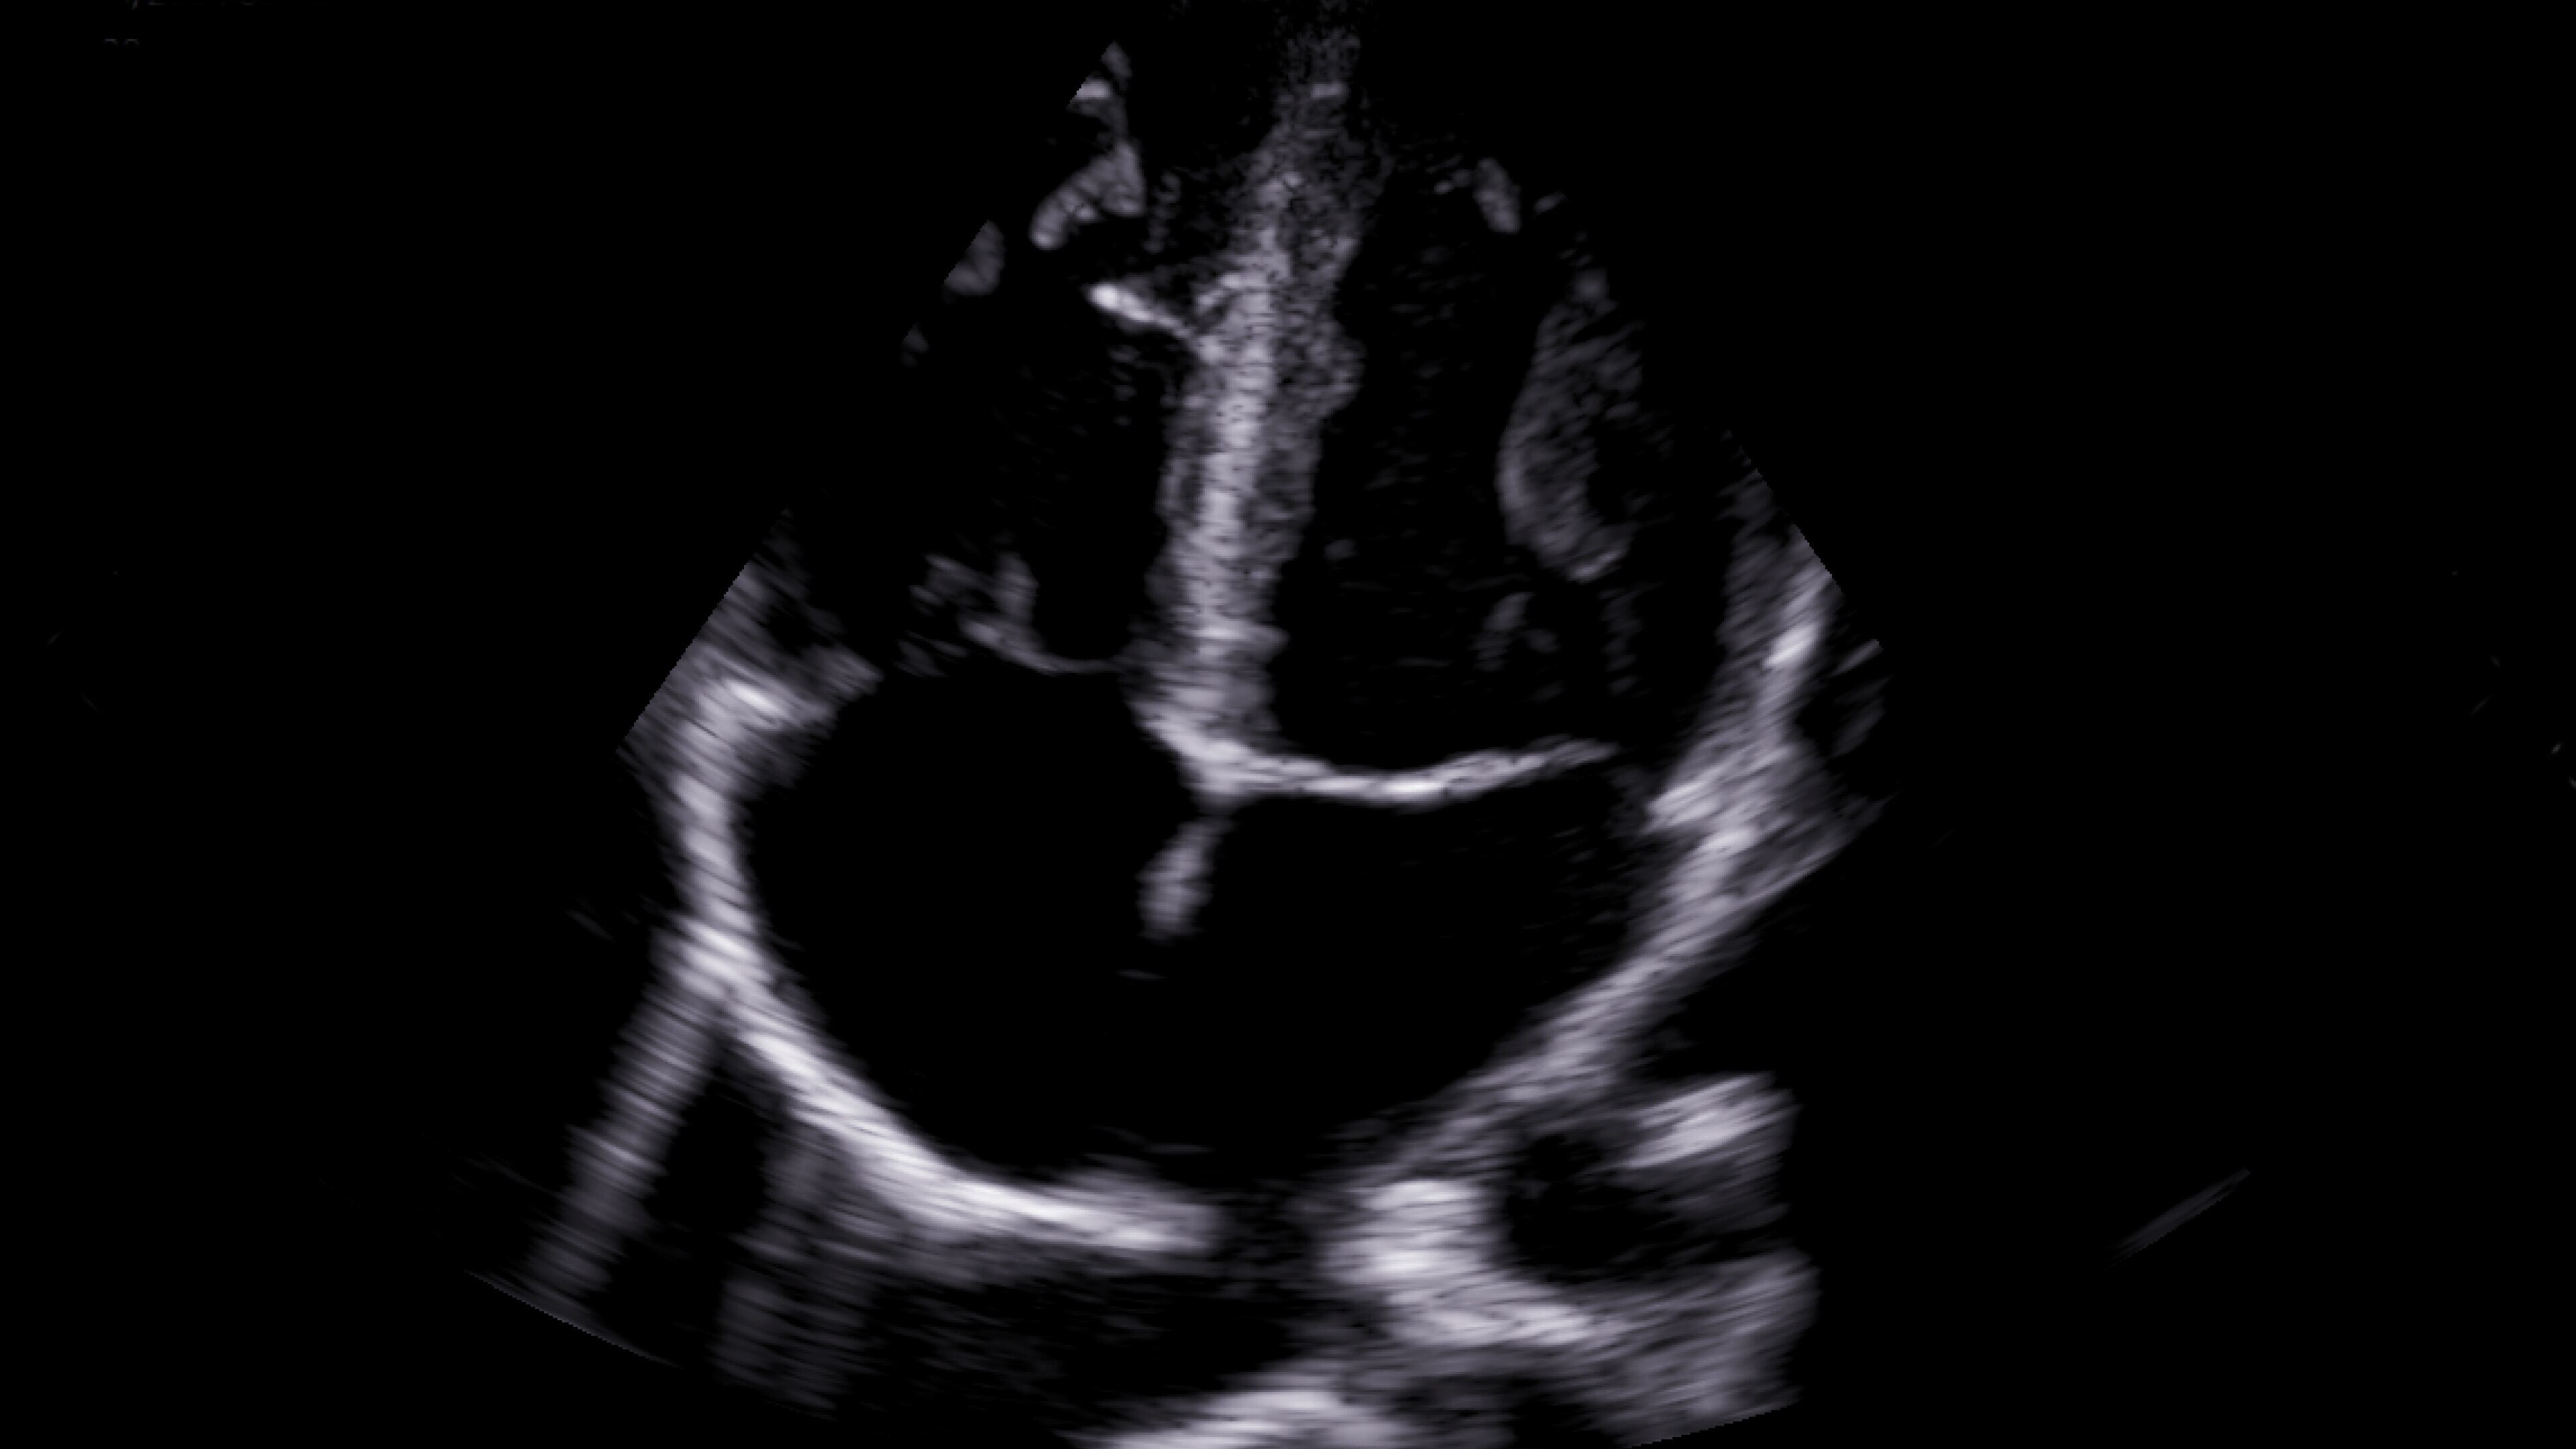

Critical care

Enables on-the-spot visual confirmation, aiding the team in decision-making and collaboration on complex cases.